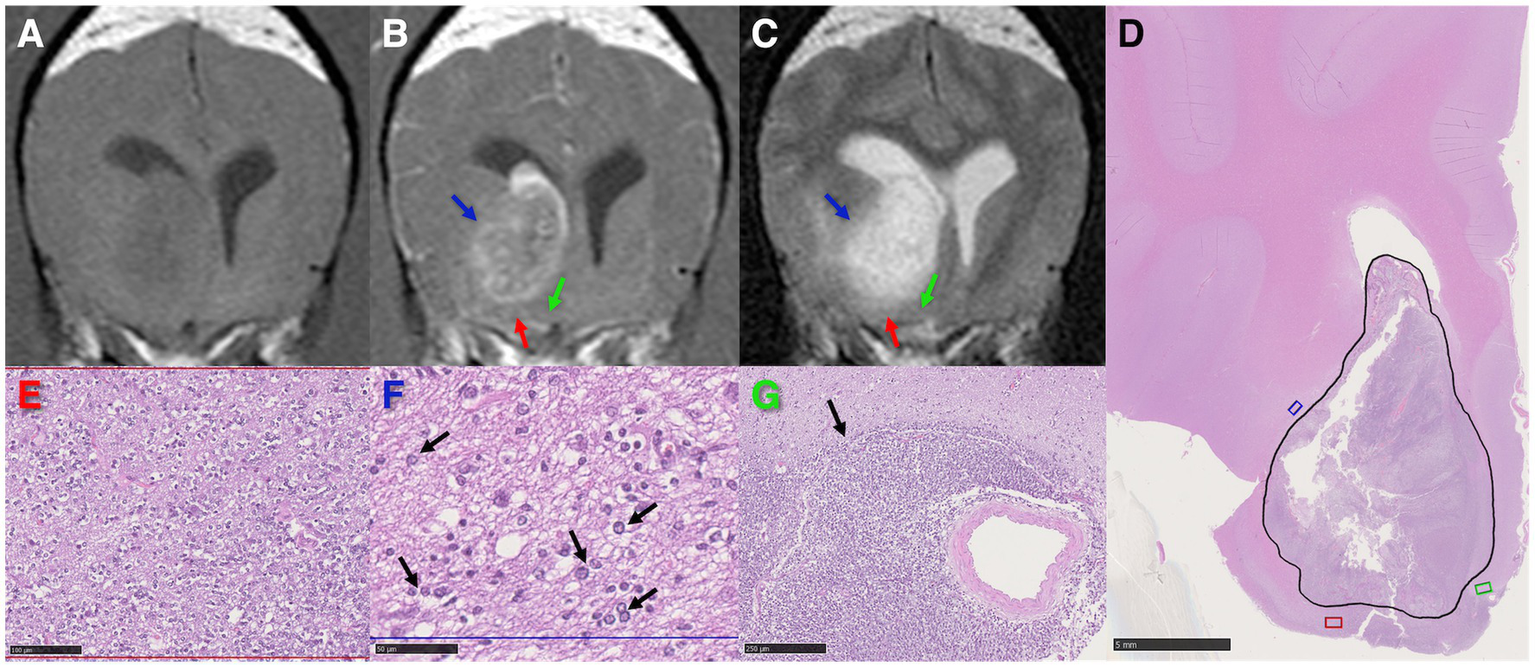

Figure 2

High-grade oligodendroglioma in the right caudate nucleus and internal capsule of a dog. (A–C) Transverse MR images demonstrating T1-weighted pre-contrast hypointensity (A), post-contrast heterogeneous and partial ring enhancement (B), and T2-weighted marked hyperintensity of the tumor (C). The red and blue arrows highlight regions of peritumoral T2-weighted hyperintensity associated with edema, the green arrow points at an area of isointense signal to grey matter in all sequences. (D) Low magnification photomicrograph with the tumor area corresponding with the partial ring-enhancing lesion on (B) outlined in black. HE stain. Scale bar = 5 mm. The red, blue, and green areas correspond to the regions pointed out by the arrows of the same color in (B, C). (E) Higher magnification of the red area in (D) revealing marked neoplastic cell invasion. HE stain. Scale bar = 100 μm. (F) Infiltrative tumor cells (black arrows) in a spongiotic neuropil (interstitial edema) in the blue rectangle in (D) coinciding with peritumoral T2-weighted hyperintensity (C) outside the partial ring-enhancing area (B). HE stain. Scale bar = 50 μm. (G) Severe infiltration by tumor cells (black arrow) of the green area in (D), apparently unaffected on MR images. HE stain. Scale bar = 250 μm.